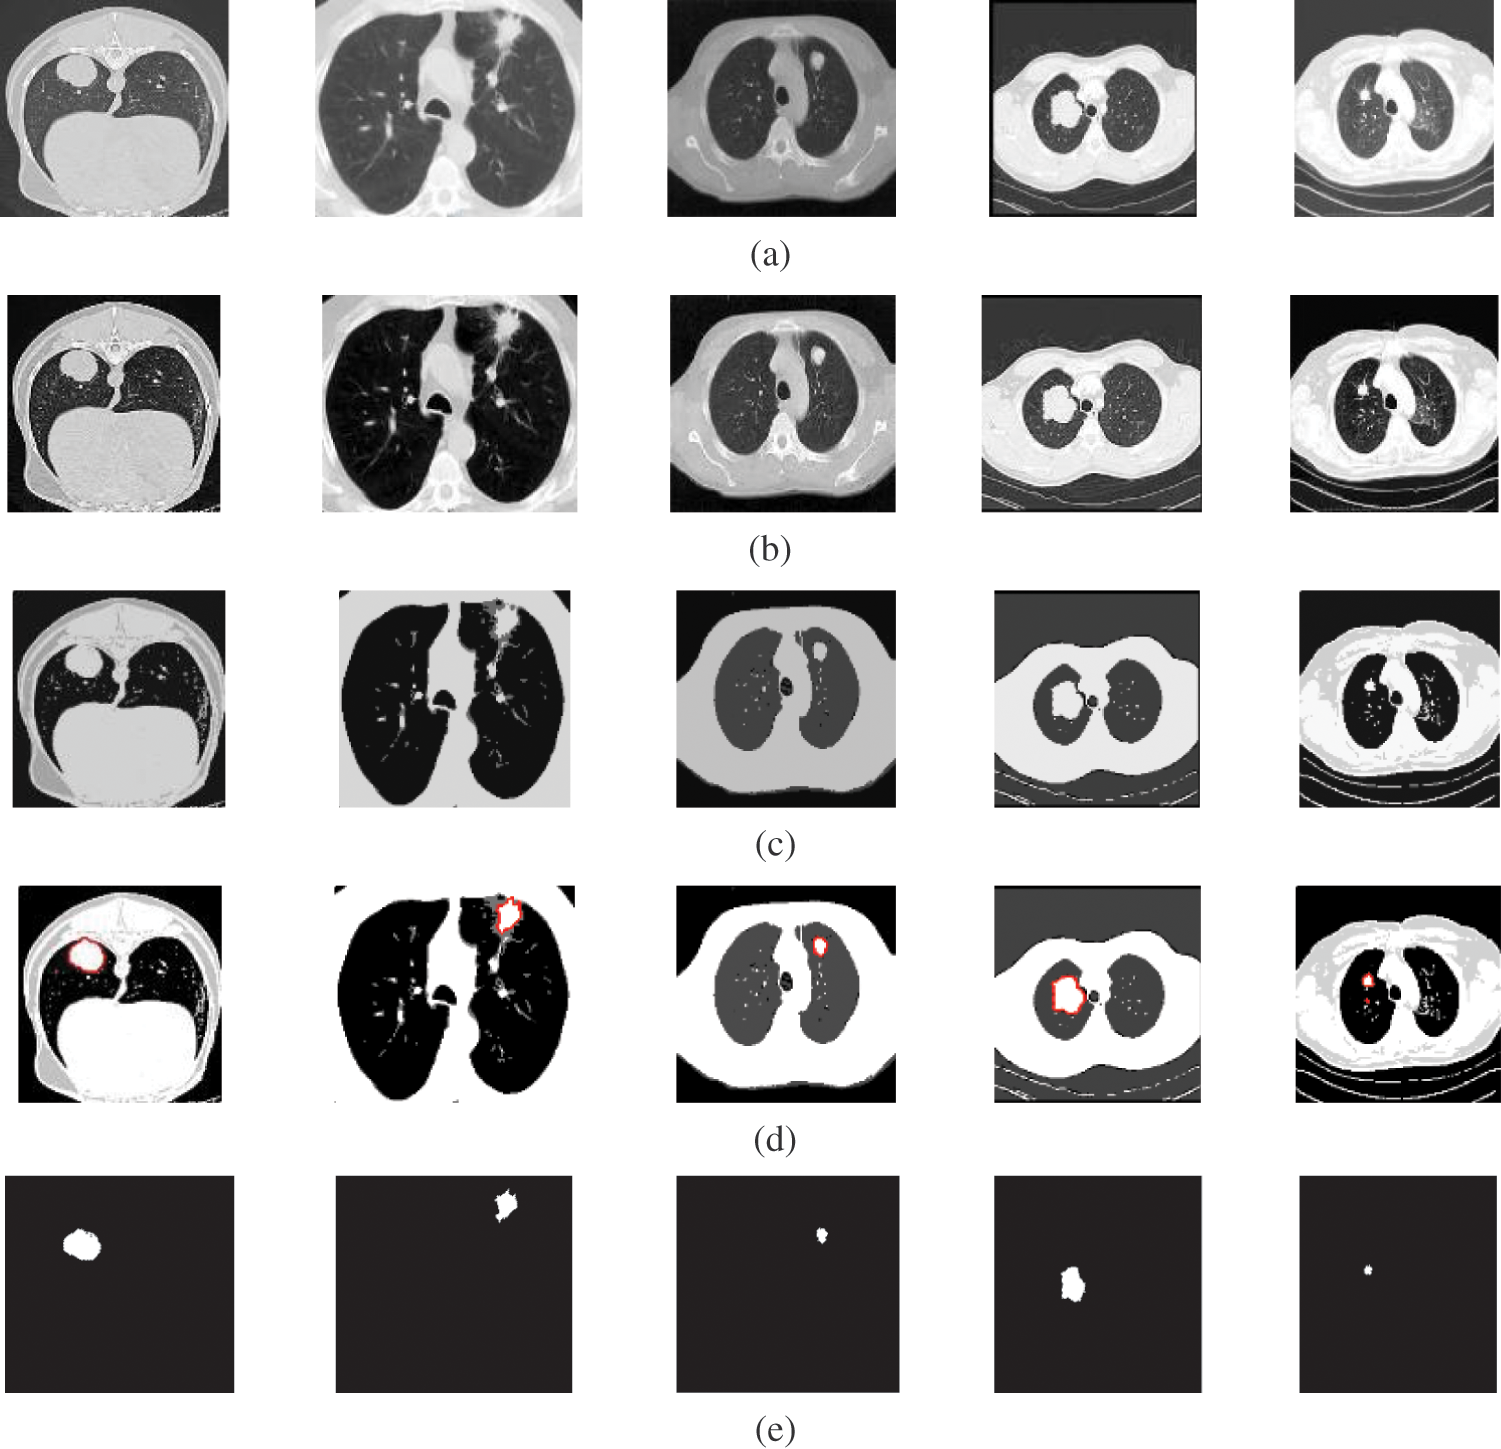

Fig. 2 shows samples of the Us breast images, Fig. 2b shows the Us images after pre-processing stage, Fig. 2c shows the FCM and morphological stage output images, Fig. 2d shows the segmentation results of the ROI produced by active contour model (the tumor is marked by a red contour), and Fig. 2e shows the resultant ROI images. Fig. 3a shows samples of the mammogram original images, Fig. 3b shows the mammogram images after pre-processing stage, Fig. 3c shows the FCM and morphological stage output images, Fig. 3d shows the segmentation results of the ROI produced by the active contour model, and Fig. 3e shows the resultant ROI images. Fig. 4a shows a sample of the CT chest images, Fig. 4b shows the CT images after pre-processing stage, Fig. 4c shows the FCM and morphological stage output images, Fig. 4d shows the segmentation results of the ROI produced by active contour model, and Fig. 4e shows the resultant ROI images.

Figure 4: A sample of the CT medical images (a) CT images, (b) CT images after preprocessing stage, (c) FCM and morphological operation output images, (d) Segmented images after active contour, and (e) The extracted tumor images

Fig. 4 illustrates the results of the proposed segmentation approach applied to the CT chest images. The enhancement results, shown in Fig. 4b, considerably enhances and improves the image contrast. The results of the morphological operations and FCM, shown in Fig. 4c, divide the images into adjacent regions as shown in Fig. 4d. Finally, the proposed approach extracts the tumors in each image, as shown in Fig. 4e. The segmentation metrics for the CT images are given in Tab. 4, and the average segmentation accuracy reached 0.9991.